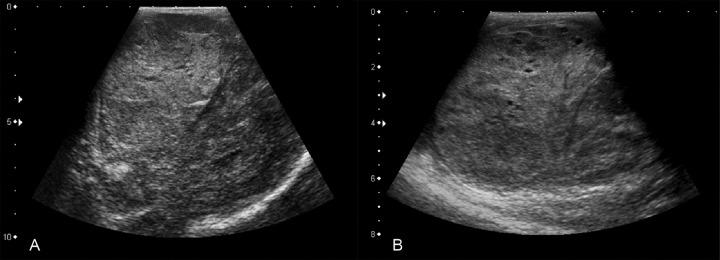

Mesothelioma of the tunica vaginalis testis (MTVT) is a rare tumor that usually affects patients after the sixth decade of life. Exposure to asbestos is a known risk factor. Enlargement of the scrotal volume is the most common initial clinical manifestation, and about 15% of cases present metastasis at diagnosis. The treatment relies on surgical resection while the role of adjuvant chemotherapy and radiotherapy remains unclear. The prognosis for patients is generally poor, with a lethal outcome in 30% over a 24-month period. The authors report a case of a 62-year-old patient with the diagnosis of MTVT without a history of asbestos exposure. After surgical treatment, metastatic disease ensued. Chemotherapy was initiated, but could not be continued due to marked and fast clinical deterioration. The authors call attention to the difficulty of early diagnosis of MTVT due to a nonspecific clinical picture, the lack of action by the patient when the scrotal enlargement was first noticed, and the lack of tumor markers. Delayed diagnosis is definitely related to unfavorable prognosis.

睾丸鞘膜间皮瘤(MTVT)是一种罕见肿瘤,通常影响60岁以后的患者。接触石棉是已知的风险因素。阴囊体积增大是最常见的初始临床表现,约15%的病例在诊断时出现转移。治疗依赖于手术切除,而辅助化疗和放疗的作用仍不明确。患者的预后通常较差,24个月内30%会出现致命结局。作者报告了一例62岁诊断为MTVT的患者,该患者无石棉接触史。手术治疗后,出现了转移性疾病。开始进行化疗,但由于明显且迅速的临床恶化而无法继续。作者提醒注意,由于临床表现不具特异性、患者首次注意到阴囊增大时未采取行动以及缺乏肿瘤标志物,MTVT早期诊断存在困难。延迟诊断肯定与不良预后相关。